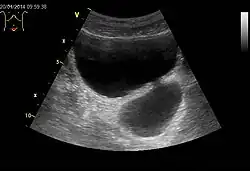

Harnblasendivertikel eines 59-jährigen Mannes, Transversalebene

Ein Divertikel der Harnblase eines Mannes in der CT-Darstellung. Sie zeigt eine Ausstülpung des Blasenlumens in Richtung des Steißbeines, siehe rechts unten. Die VR-Darstellung links oben zeigt den mit einem Kreis beschriebenen Bereich.